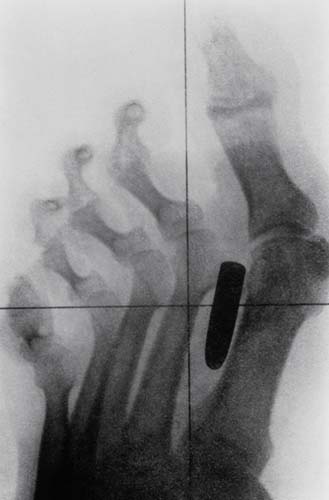

Tarihten bir röntgen filmi. Bir askerin ayak parmaklarının arasına saplanmış bir kurşun.